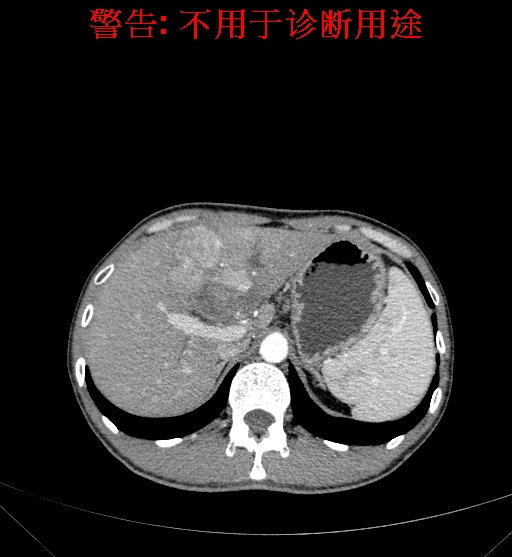

上腹部CT动态增强扫描示肝左叶多发占位性病变,考虑肿瘤,建议MR平扫+增强进一步检查。上腹部MR动态增强示肝左叶肝Ca挤压肝门区结构可能性大,请结合临床综合评价。

术前CT检查:

动脉期

静脉期